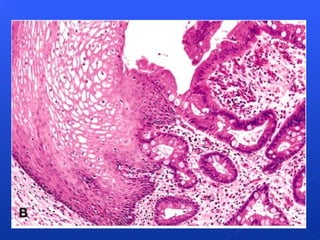

Proliferative endometrium

Atrophic endometrium

Atrofia glandular

prostática: epitelio

glandular  prostático

aplanado, (H&E).